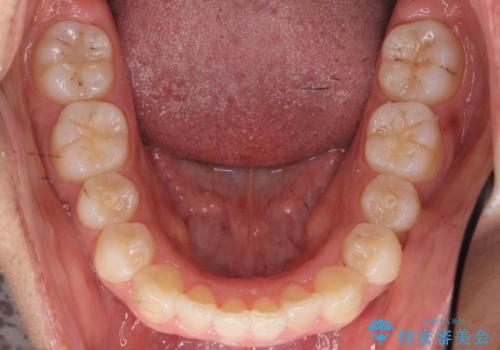

リファインメントもなく、1回で治療が終了しました。大変うまくいったケースです。

抜歯をしていないので口元は変わっていません。

八重歯も重症でなければインビザラインでも並びを歯を抜かずに整えることができます。